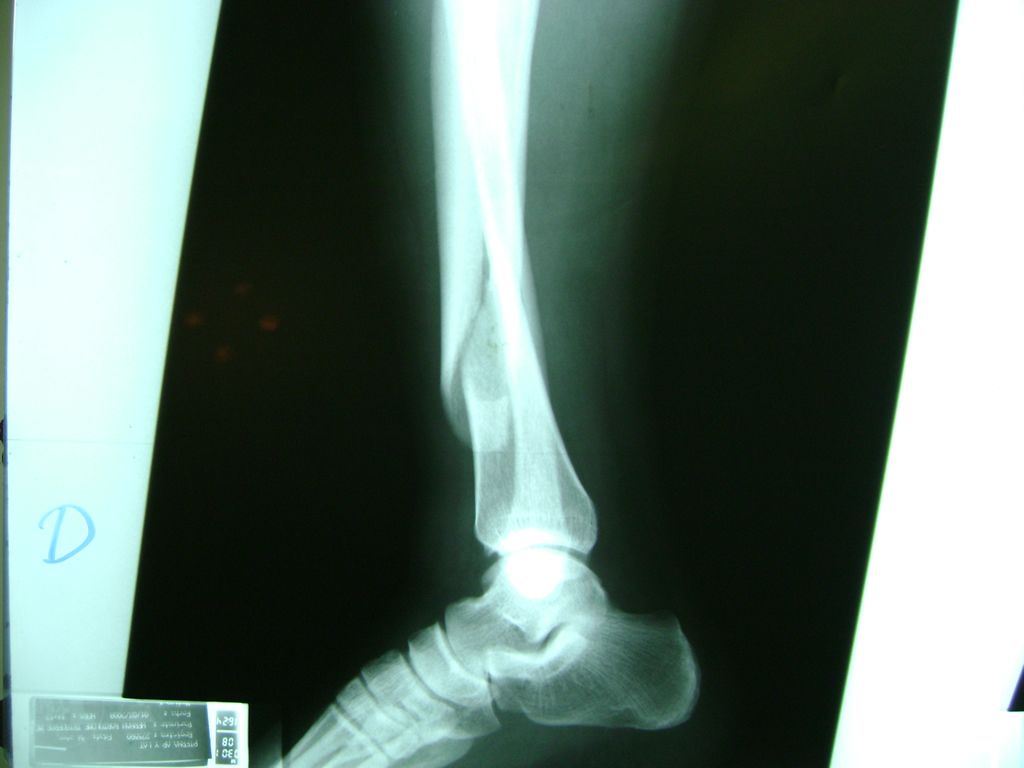

Aunque cada uno de estos huesos puede fracturarse por separado, normalmente la rotura es una lesión que se produce de forma conjunta

La mayor parte de las roturas implican a la parte proximal del hueso (parte del hueso próximo a la rodilla) o a la parte distal (parte del hueso cerca del tobillo).

Debido a la fina cobertura de piel que recubre la tibia y el peroné, las fracturas generalmente son abiertas, es decir, el hueso roto rasga la piel, atravesándola. Las fracturas de tibia y peroné generalmente se producen por un fuerte impacto o torsión.